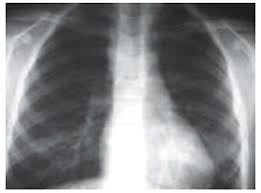

A tuberculose é provocada por uma bactéria que ataca geralmente os pulmões, sendo transmitida por gotículas eliminadas para o ar pela tosse do doente.

A radiografia(Imagem á esquerda) dos pulmões ajuda o médico a diagnosticar a tuberculose(embora essa doença não ataque apenas os pulmões).